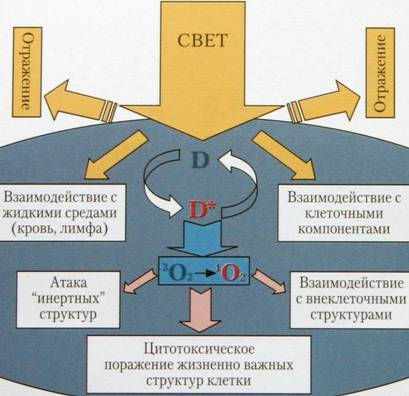

Метод ФДТ основан на способности молекул фотосенсибилизаторов (ФС), азот-содержащих веществ с макроциклической химической структурой, селективно накапливаться в опухолевой и патологически измененной ткани и под действием квантов света определенной длины волны вызывать фотохимическую реакцию, приводящую к избирательной гибели раковых или микробных клеток .

Фотохимическая реакция, протекающая в опухоли с образованием синглетного кислорода и других высокоактивных частиц, оказывает повреждающее действие на раковые клетки и сосуды стромы опухоли, в результате чего опухоль гибнет и замещается соединительной тканью. Подобная фотохимическая реакция становится возможной, когда на фотосенсибилизатор, накопившийся в опухоли, воздействуют светом достаточной мощности и длиной волны излучения, совпадающей с пиком поглощения света этим ФС (Minnock A et al., 1996) (рис. 1).

Рис. 1. Схема распределения энергии в процессе ФДТ.

• D – фотосенсибилизатор.

• D * – возбужденный фотосенсибилизатор.

• 3 О 2 – кислород тканей.

• 1 О 2 – синглетный кислород.